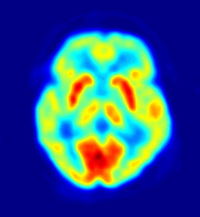

وتمكن تقنيتان جديدتان مأمونتان هما: التصوير المقطعي بابتعاث البوزيترونات والتصوير بالرنين المغنطيسي الوظيفي، العلماء من دراسة الدماغ السليم أثناء عمله. ولاتتطلب هاتان التقنيتان اتصالاً مباشرًا بالدماغ، ولكنهما ينتجان صورًا شبيهة بصور الأشعة السينية، والتي توضح أي أجزاء الدماغ يعمل أثناء أداء الشخص نشاطًا ذهنيًا أو بدنيًا، حيث يوضح التصوير المقطعي بابتعاث البوزيترونات أجزاء الدماغ الأكثر استهلاكًا للجلوكوز، بينما يوضح التصوير بالرنين المغنطيسي الوظيفي، الأجزاء التي يشير فيها استهلاك معدلات عالية من الأكسجين إلى نشاط الجزء.

في أواخر القرن التاسع عشر، لاحظ العلماء أن تدمير جزء معين من الدماغ، يسبب نفس العجز اللغوي في معظم المرضى. فالتدمير الذي يصيب الفص الجبهي الأيسر في منطقة بروكا، والتي سميت على اسم الجراح الفرنسي بيير باول بروكا، يدمر بدوره القدرة على الكلام، بينما يسبب التدمير الذي يلحق بالفص الصدغي الأيسر، في منطقة فيرنك، التي سميت على اسم عالم الأعصاب الألماني كارل فيرنك، صعوبات في فهم اللغة. وقد قادت هذه الملاحظات العلماء إلى الاعتقاد بأن الدماغ يعالج الكلمات في مراحل منظمة، عبر سلسلة من المناطق ذات الصلة باللغة. ولكن باستخدام تقنيات تصوير معينة، مثل التصوير المقطعي بابتعاث البوزيترونات والتصوير بالرنين المغنطيسي الوظيفي، يستطيع العلماء مراقبة الدماغ مباشرة أثناء التحدث أو الاستماع أو القراءة أو التفكير. وقد أوضحت الدراسات المبنية على هذه التقنيات أن معالجة اللغة أمر بالغ التعقيد. فمناطق اللغة تحتل مساحات واسعة من الدماغ، وتنشط أنواع متباينة من المهام اللغوية هذه المناطق بطرق وأنماط مختلفة.